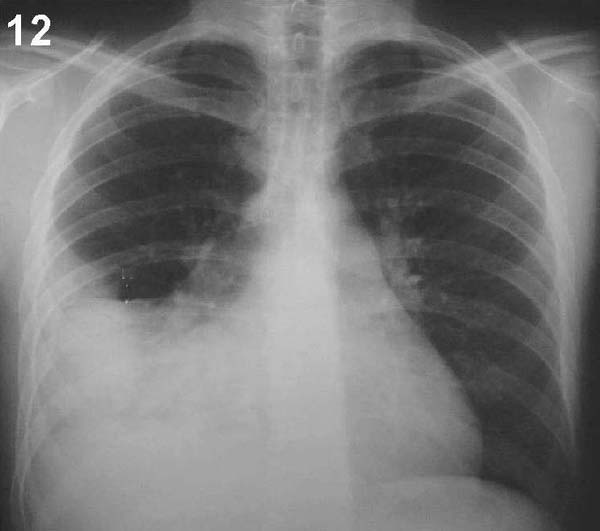

PLACA 12